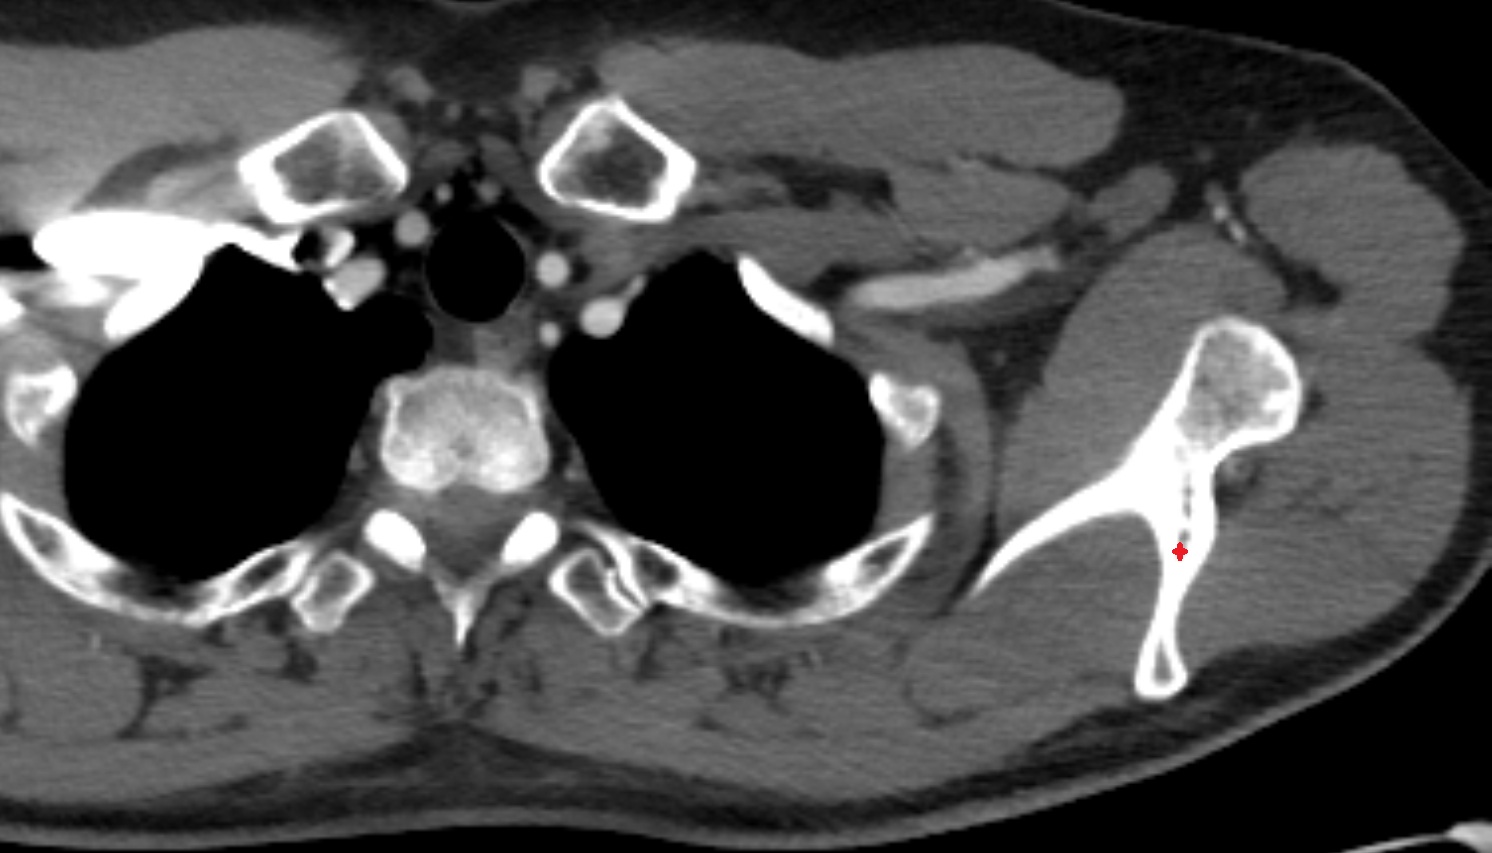

- Glenoid fossa

- Glenoid process of scapula

- Spine of scapula

- Acromion process of scapula

- Coracoid process of scapula

- Scapular body

- supraspinous fossa of scapula

- Subscapular fossa

- Neck of scapula